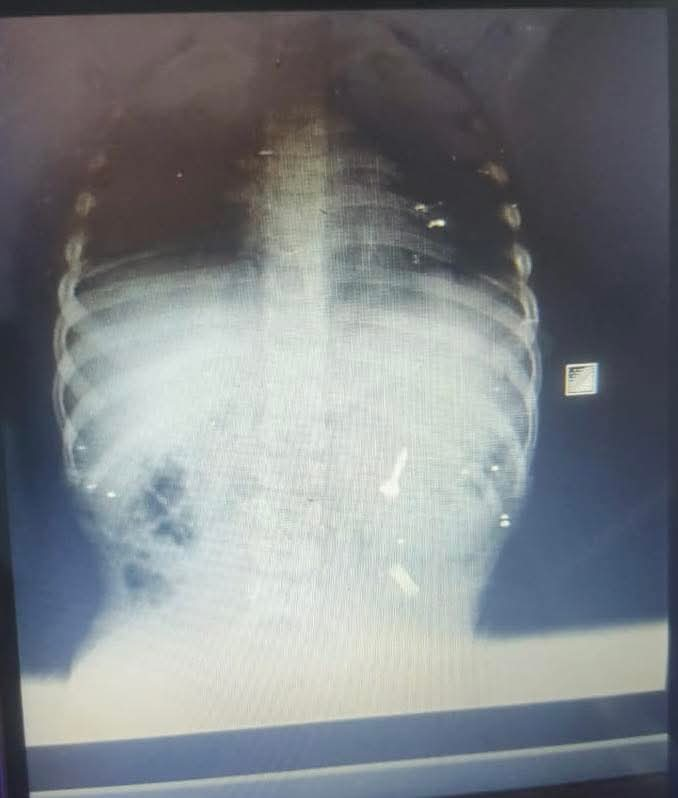

بدأت الأحداث ، حين وصلت أسرة الطفل إلى قسم الطوارئ بمجمع الشفاء الطبي التابع للهيئة العامة للرعاية الصحية بفرع بورسعيد ،وهي في حالة هلع شديد، ليتم استقباله فورًا وإجراء أشعة عاجلة على البطن لتحديد موقع الجسم الغريب.

وأظهرت الصور وجود المسمار في أول أجزاء الأمعاء الدقيقة المصران الصائم، وهو موقع يصعُب الوصول إليه بالمنظار نظرًا لوجود تعرجات وزوايا ضيقة، مما جعل احتمالات التنظير محدودة للغاية.